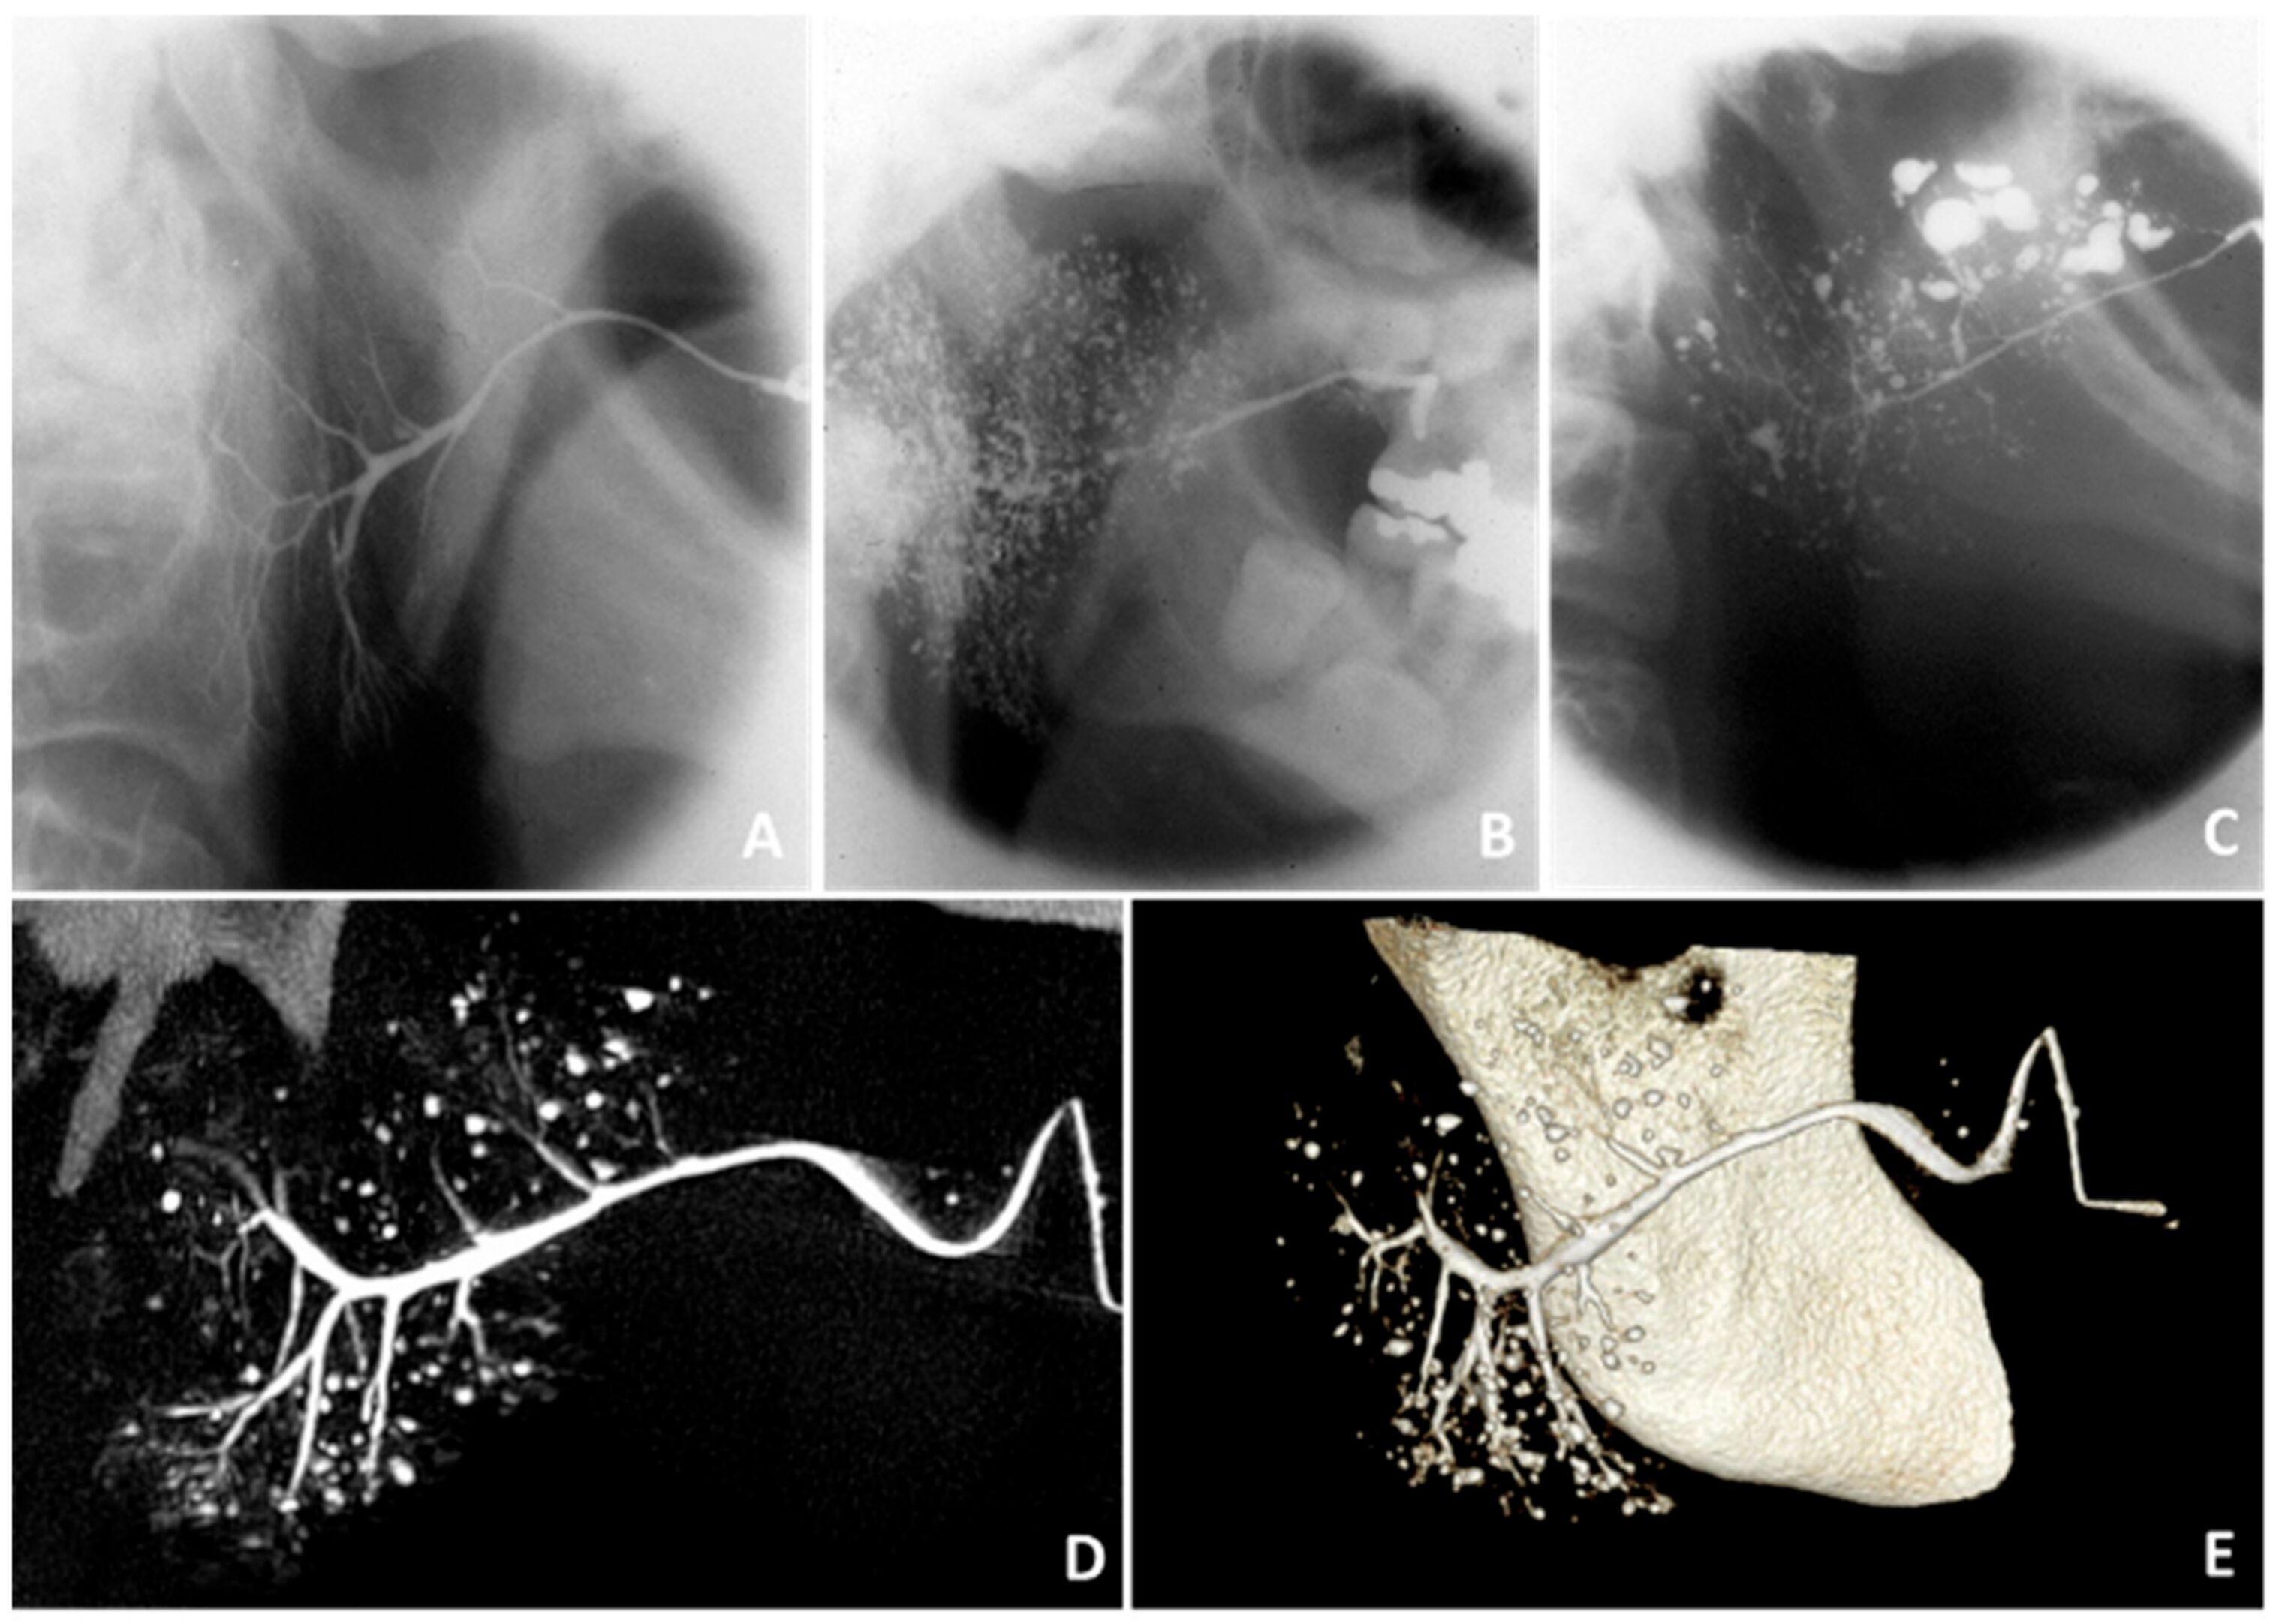

Figure 2. Findings on sialography. Sialographies of the parotid gland showing (A) no abnormalities in a healthy subject, (B) punctate/globular sialectasis in a pSS patient, and (C) globular/cavitary sialectasis in a pSS patient [29]. (D) Two-dimensional sialo-CBCT image and (E) three-dimensional sialo-CBCT image of the parotid gland of a pSS patient, showing normal width of the primary duct, moderate scarcity of ductal branches, and numerous diverse sialectasis. Thanks to Prof. D.J. Aframian and Dr. C. Nadler and colleagues who provided the sialo-CBCT images.